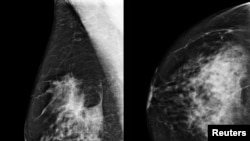

A yellow box indicates where an artificial intelligence (AI) system found cancer hiding inside breast tissue, in an undated photo released by Northwestern University in Chicago, Jan. 1, 2020.

A Google artificial intelligence system proved as good as expert radiologists at detecting which women had breast cancer based on screening mammograms and showed promise at reducing errors, researchers in the United States and Britain reported.

The study showed the AI system could identify cancers with a similar degree of accuracy to expert radiologists, while reducing the number of false positive results by 5.7% in the U.S.-based group and by 1.2% in the British-based group.

It also cut the number of false negatives, where tests are wrongly classified as normal, by 9.4% in the U.S. group, and by 2.7% in the British group.